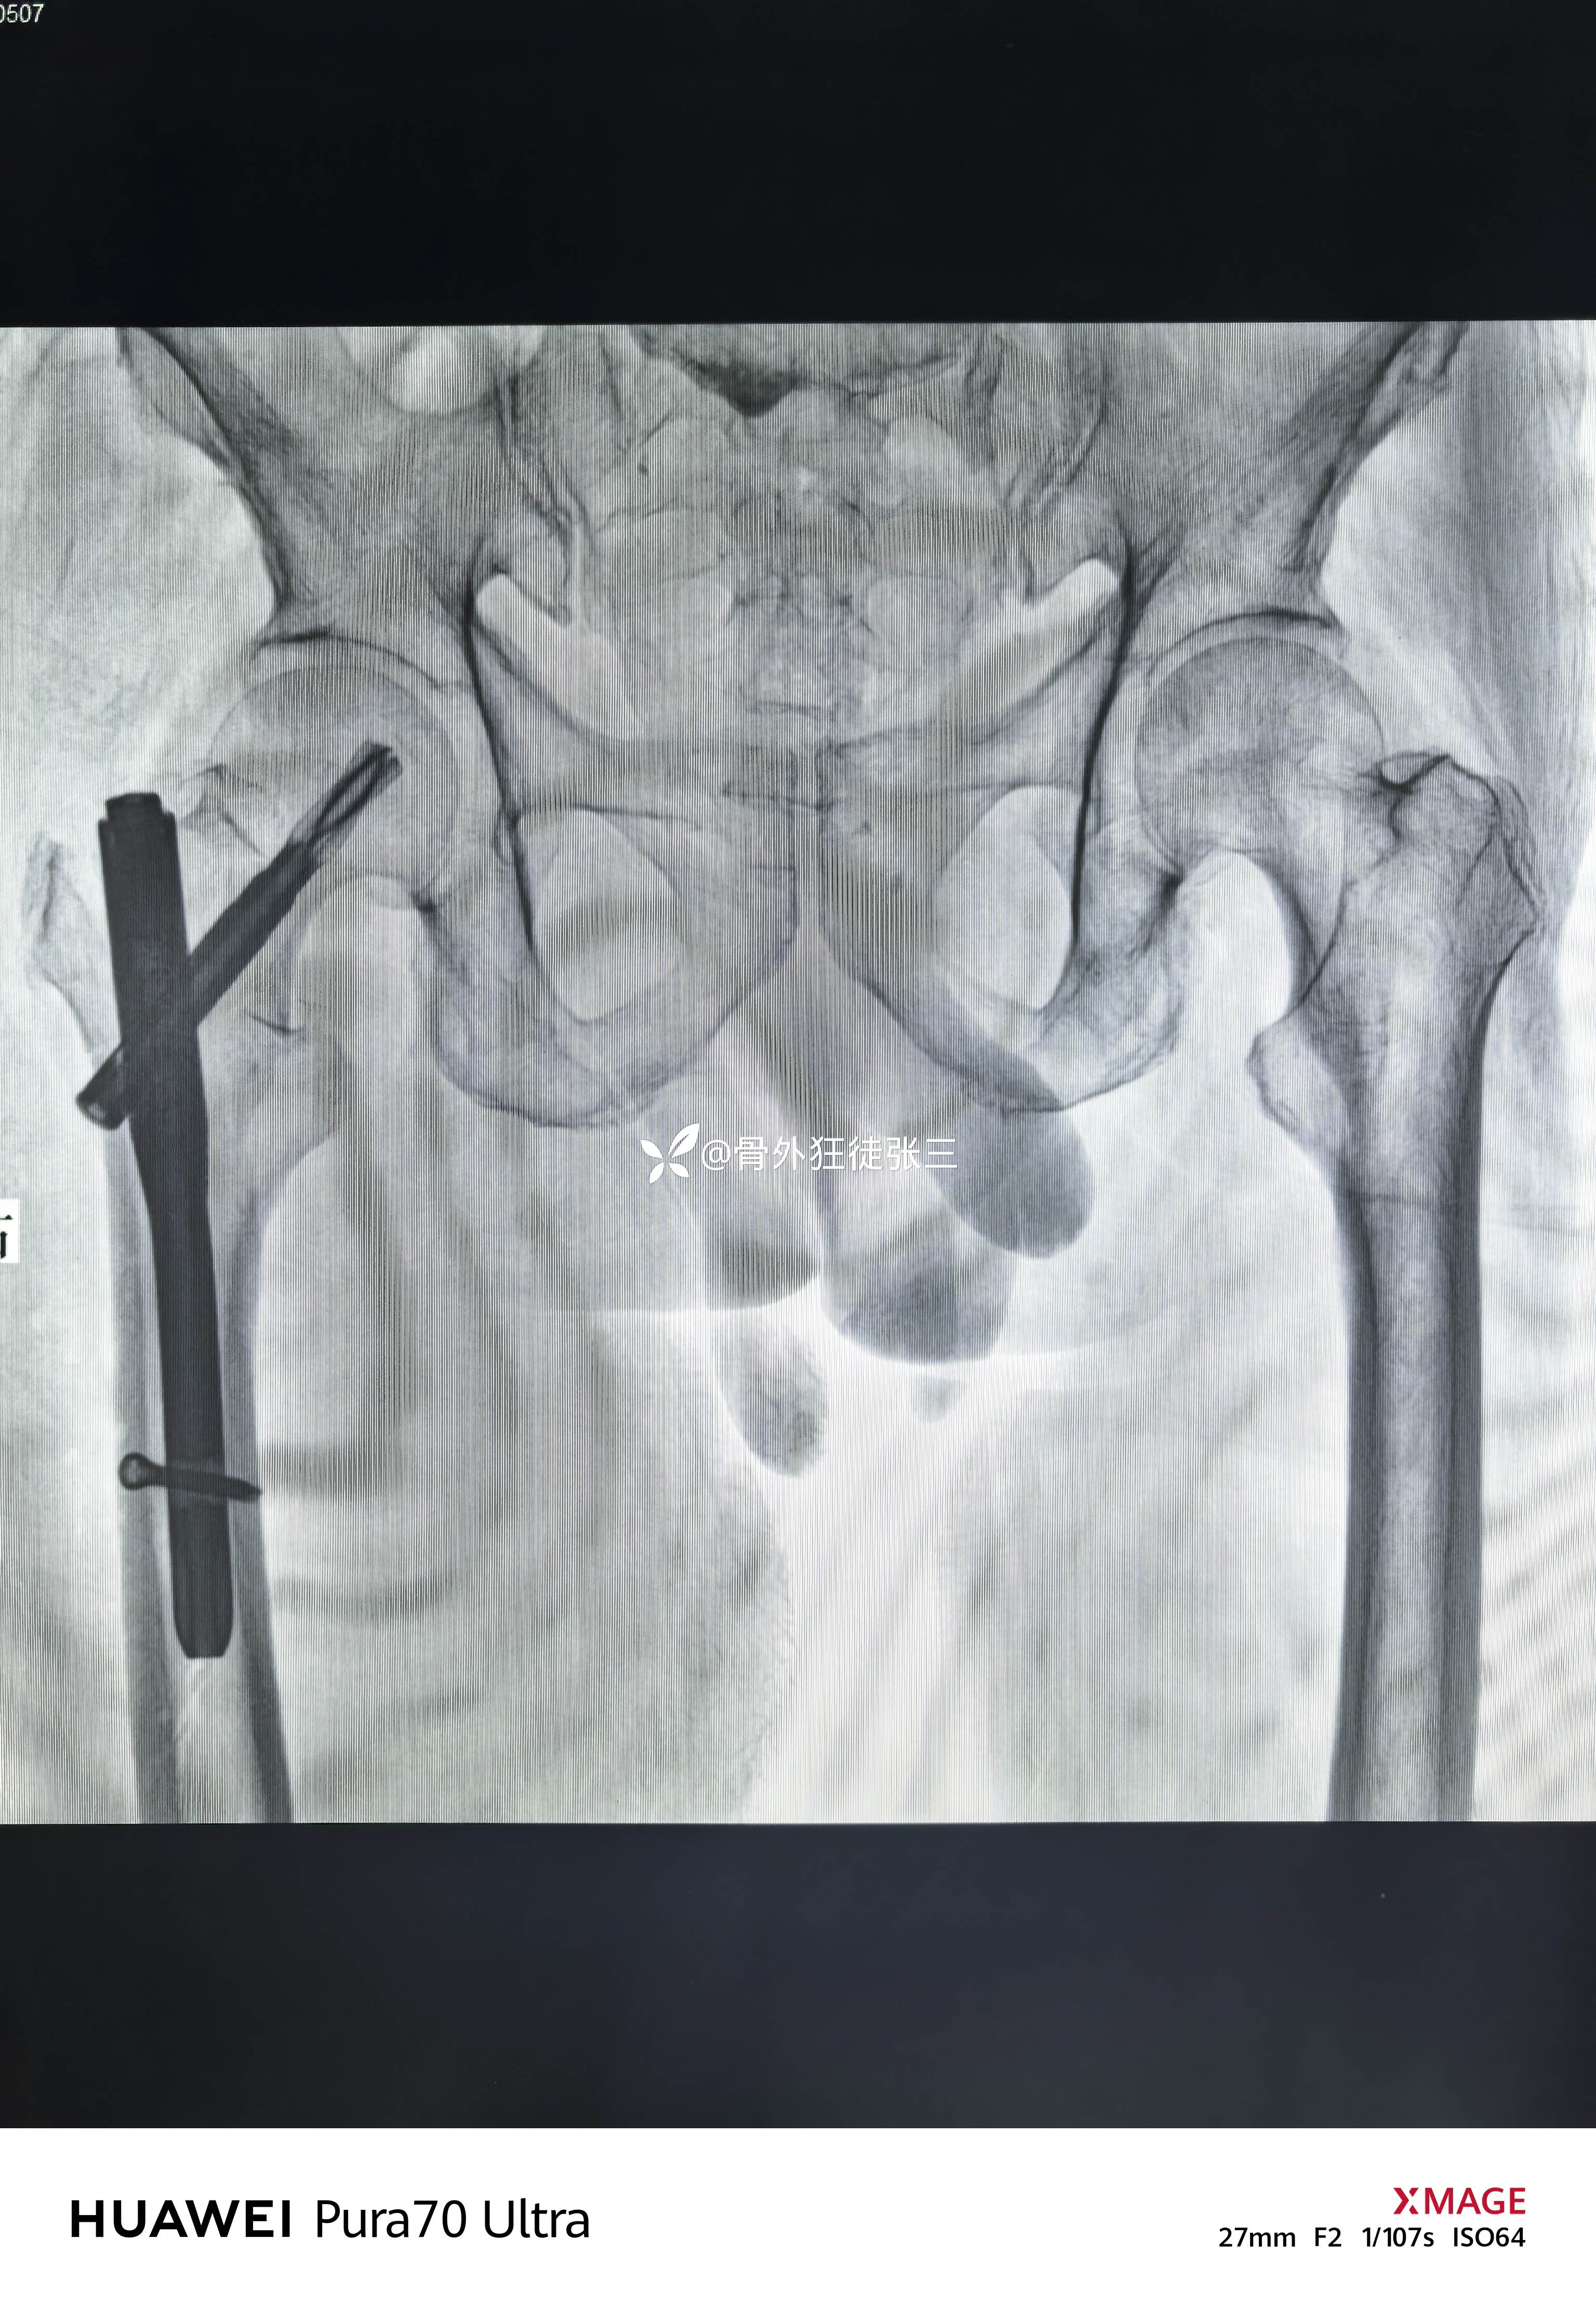

曹谦湘潭市中医院 等 2 位达人已点赞患者性别:男

患者年龄:82岁

主诉:摔伤右髋部致肿痛、畸形、活动受限5天。

右股骨转子间骨折

牵开器——透视正侧位——切口——确定进针点——铰刀开口——开口钻开口——金手指——导针置入——直接使用170 mmX12 mm主钉插入——调整前倾主钉深度和前倾——透视正位中下1/3,侧位基本居中——远端锁钉——近端锁尾端尾帽,——再次透视正、侧、蛙位——冲洗、缝合1-1-3 ——09:37-10:16 ——40分钟手术结束,透视16次,每次约一分钟,手术操作20分钟。

没有再调整主钉和螺旋刀片

术后复查

螺旋刀片还能再长5mm